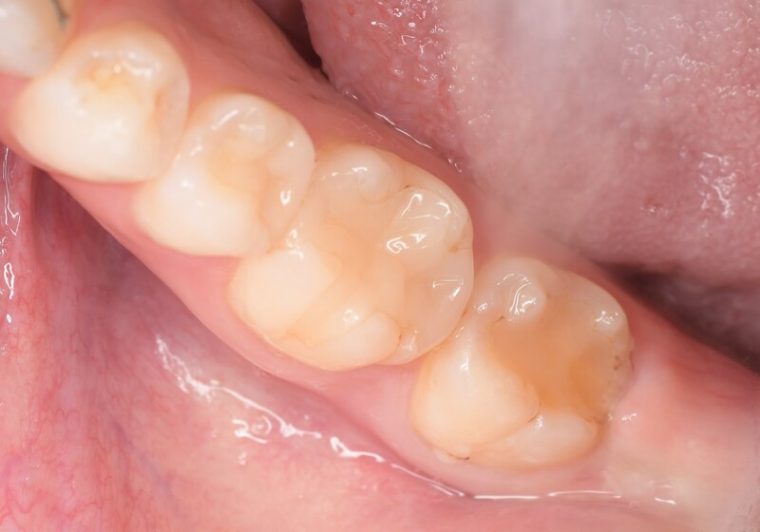

after

症例

年齢・性別 28歳・女性

主訴 右下7番の歯肉の厚みが気になる。

治療内容 歯肉を切除する周辺に麻酔をし余分な歯肉と結合組織を一部切除し歯肉を縫合します。二週間後に抜糸を行います。

治療期間 2週間

治療費 合計 2,000円(保険適用3割負担)

(2023年3月現在)

リスク・副作用 ・歯肉を一部切除する為、数日痛みがでることがあります。

・歯肉切除した歯にしみる症状がでる可能性があります。

特記事項 外科治療の為、当日の運動やお酒など血流がよくなる行動はお控えください。

担当者所見

抜糸の際、術後の痛みはほとんどなく歯肉の厚みがなくなり清掃しやすくなったと患者様がおっしゃっていました。